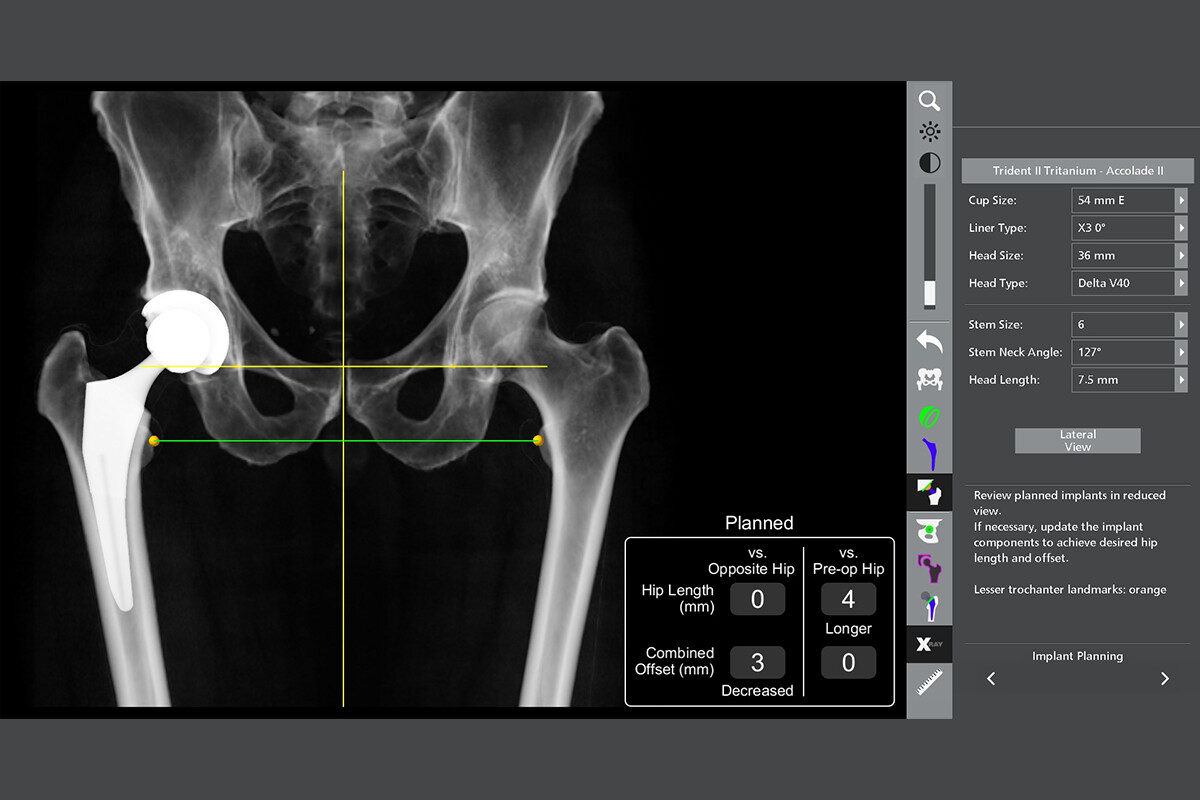

Dr. Duff is highly experienced in advanced joint reconstruction techniques, including:

These procedures are tailored to your anatomy, activity level, and long-term goals. Many patients report a dramatic improvement in mobility, independence, and quality of life after surgery.